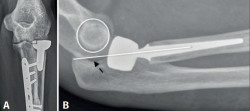

Radiológicamente, podemos cuantificar el exceso de longitud midiendo la distancia entre el margen lateral de la apófisis coronoides y el límite superior del implante, siendo posible apreciar esclerosis, geodas e irregularidad del capitellum. En casos de inestabilidad posterior secundaria al exceso de longitud, el eje longitudinal del radio será posterior al epicóndilo (drop sign) (Figura 2).

Figura 2. A: exceso de longitud y degeneración secundaria del capitellum; B: inestabilidad posterior o drop sign(7).